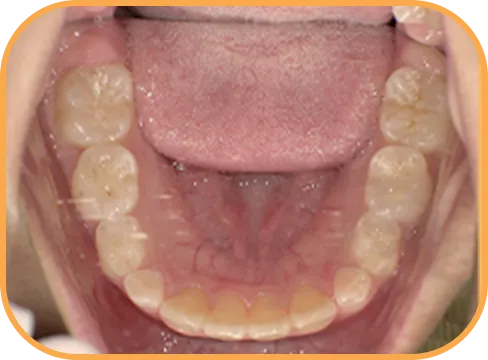

• Before

• 正 面

治療前正面からの歯の様子

• 上 顎

治療前上顎からの歯の様子

• 下 顎

治療前下顎からの歯の様子

• 右 側

治療前右側からの歯の様子

• 左 側

治療前左側からの歯の様子

主 訴

前歯が開いている

治療内容

インビザライン・ファースト

治療期間

6か月

治療費(税別)

450,000円+診断料30,000円

リスク・副作用

• 親知らずの影響や加齢などによって、凸凹が生じる可能性があります。

• 治療の初期段階では痛みや不快感が生じやすくなりますが、1週間前後で慣れます。

• 顎の成長発育によって、噛み合わせや歯並びが変化する可能性があります。

• 状況により当初予定した治療計画を変更する可能性があります。